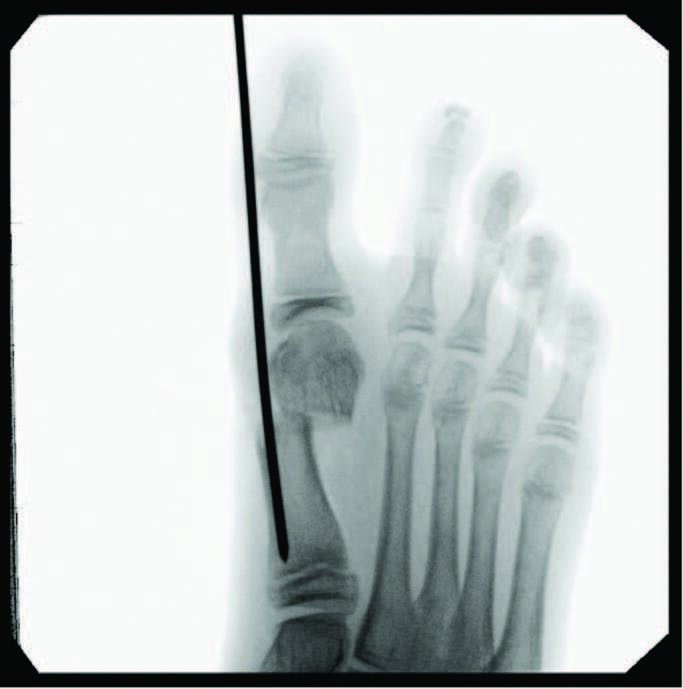

Minimally Invasive Approaches To Juvenile Hallux Abducto Valgus Deformity

Juvenile hallux abducto valgus (HAV) deformities affect approximately 36 percent of the pediatric population, predominately female.1 One can attribute juvenile HAV deformity to congenital, neurogenic, idiopathic etiologies, and/or biomechanical compensatory changes.1 During the physical exam, one must examine and rule out congenital deformities to accurately determine the best treatment options. It is also important to consider the neuromuscular influences of cerebral palsy and myotonic dystrophy, as well as joint laxity-associated disorders like Marfan and Ehlers-Danlos syndromes.2 Though pain and function help drive a provider’s decision-making process, parental concerns with difficulty finding adolescent shoes to accommodate the HAV must also be a consideration in the treatment decision-making process.

Predictors of juvenile HAV severity, in addition to subtalar joint pronation, include: rounding of the first metatarsal head; an atavistic cuneiform; a hypermobile or long first ray; and a high metatarsus primus adductus angle.4 Additional pes planus-related radiographic measurements include an increased first intermetatarsal angle, reported in 26.6 percent of adolescents and an increased metatarsus primus varus angle in 8.1 percent.5 Anatomic abnormalities such as Achilles equinus contractures, digital contractures, syndactyly, metatarsus adductus, hereditary exostoses, and congenital hip dislocation may need attention for long-term successful HAV treatment. Other considerations include brachymetatarsia, where a shortened lesser metatarsal leads to an abnormal transverse metatarsal parabola, allowing more lateral deviation of the hallux and increased metatarsus varus angle due to soft tissue balancing effects.

A myriad of open and minimally invasive (MIS) surgical procedures exist for this patient population, with various long-term data demonstrating outcomes, complications, and failure rates. While the literature skeptically portrays early percutaneous procedures, in my experience modern developments in technology have led to much-improved outcomes and techniques, albeit with a lack of long-term data to explain why surgeons continue to shy away from such methods. Minimizing failure rates and increasing patient satisfaction of hallux valgus correction is an important objective of surgeons continuing to improve on traditional methods. The ability of MIS to allow early mobilization by utilizing the same AO principles of traditional methods and the ease of reproducible triplanar correction continues to be a motivation, in my observation, to advance this newer approach and increase its utilization in the podiatric surgical field.

Although minimally invasive hallux valgus surgery is a more modern technique, especially for the pediatric population, it still relies, in my experience, on AO principles of fracture fixation, including anatomic reduction in the first intermetatarsal and hallux abductus angles, stable fixation, preservation of blood supply, and early active mobilization. I find the percutaneous approach allows the reduction of a wide range of mild to severe radiographic angles and preservation of blood supply. In a study of minimally invasive bunion procedures, surgeons achieved up to a 12.5 degree correction of the first intermetatarsal angle and reported a 5.3 percent reoperation rate. The study was from a surgeon’s first 94 MICA procedures, and the author challenged the previously reported steep learning curve, citing low complication rates and ease of reproducibility.13